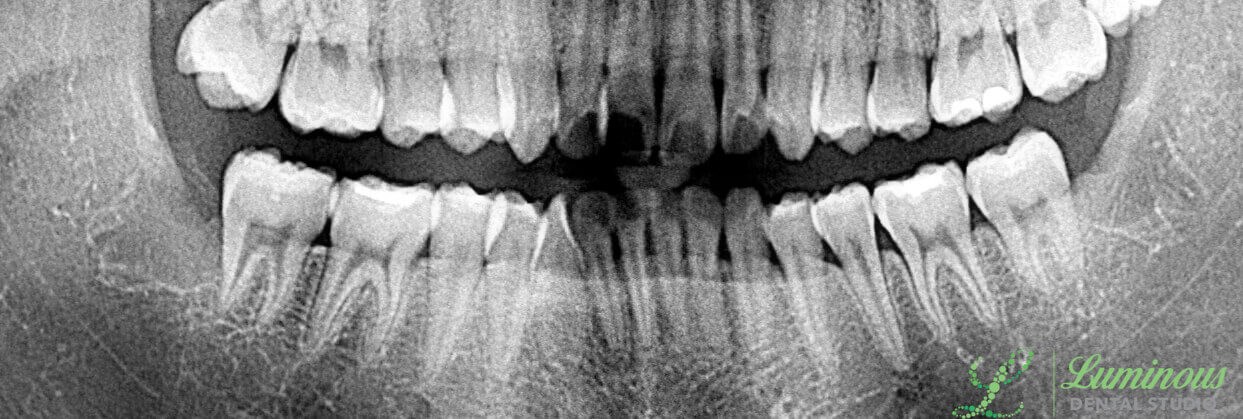

Impacted third molars extracted in Frisco, TX by Minho Chang DMD.